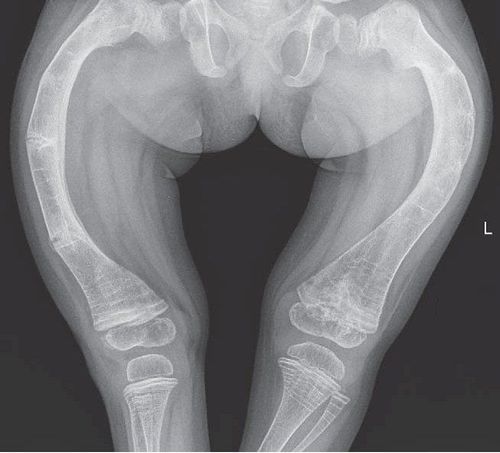

Viêm khớp dạng thấp có thể dẫn đến tổn thương khớp vĩnh viễn và biến dạng khớp.

Viêm khớp dạng thấp có thể dẫn đến tổn thương khớp vĩnh viễn và biến dạng khớp